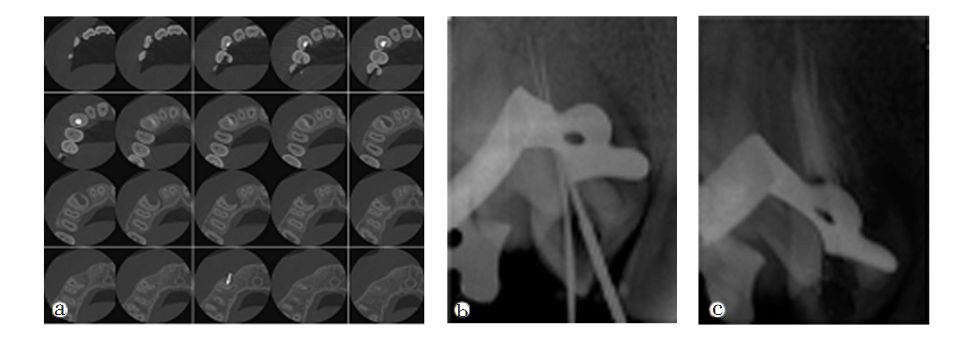

牙齒根管治療中如忽略根管治療,則會導致這個區域根管系統不可以完全清理工作嚴實添充,無法爲齲病和慢性牙髓炎痊愈給予最理想的標准,造成牙齒根管治療不成功。因而,根管治療忽略即是牙齒根管治療裏的錯誤操作之一,也是危害牙齒根管治療愈後的重要因素之一。

主莖管忽略的處理方法